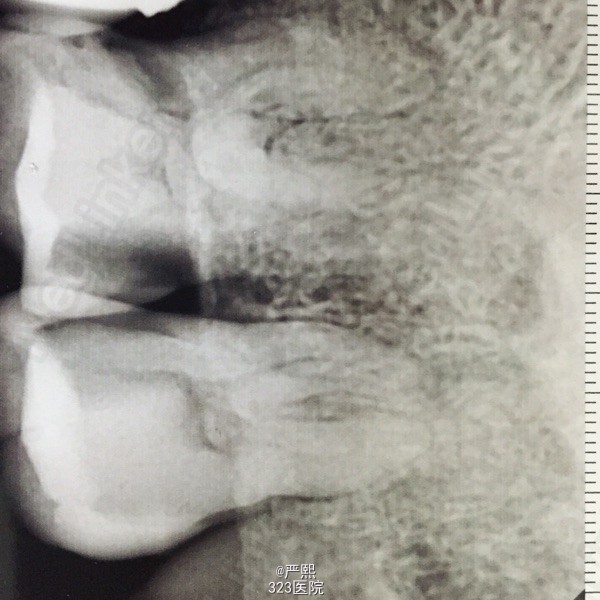

检查:26,27吻合邻面深龋坏,冷测极敏感,探痛明显,叩(+),松(-)。 辅助检查:RVG示26,27吻合邻面深龋坏,龋深及髓。26,27髓腔内可见大块髓石。

诊断:26,27牙髓炎 26,27髓石。 处理:26,27局麻下开髓,低速手机去除髓石,建立根管直线通路。Protaper扩至F1,测长:26,P:19mm,MB:18mm,DB:18.5mm。 27,P:18mm,MB:17mm,DB:17.5mm。双氧水生理盐水交替冲洗,试胶,干燥根管,封木棉。一周后复诊根管充填。